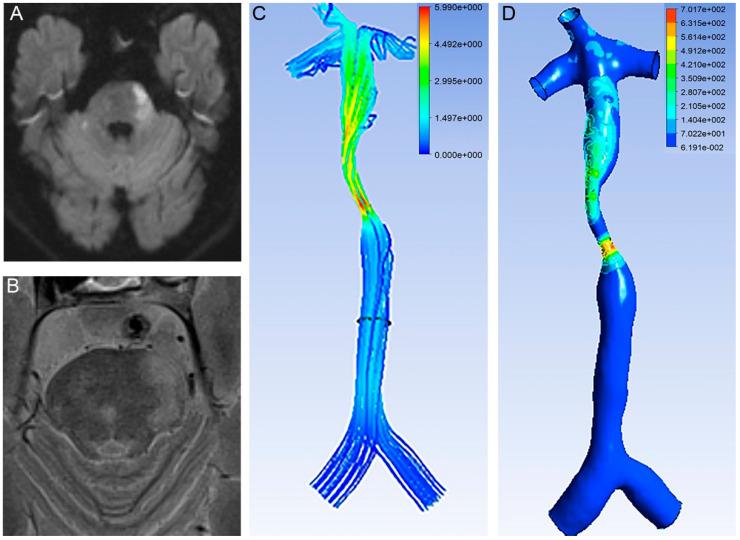

Plaque rupture of the basilar artery is one of the leading causes of posterior circulation stroke. The present study aimed to investigate the role of fluid dynamics in the ruptured fibrous cap of basilar artery plaques. Patients with basilar artery plaques (50−99% stenosis) were screened. Integrity of the fibrous cap was assessed by high-resolution MRI. Computational fluid dynamics models were built based on MR angiography to obtain the wall shear stress and velocity. A total of 176 patients were included. High-resolution MRI identified 35 ruptured fibrous caps of basilar artery plaques. Ruptured fibrous cap was significantly associated with acute infarction (27/35 vs. 96/141, p < 0.05) in the territory of the basilar artery. Proximal wall shear stress of stenosis was positively related with the ruptured fibrous cap (OR 1.564; 95% CI, 1.101−2.222; p = 0.013). The threshold of wall shear stress for the ruptured fibrous cap of basilar artery plaques was 4.84 Pa (Area under ROC 0.732, p = 0.008, 95%CI 0.565−0.899). The present study demonstrated that increased proximal wall shear stress of stenosis was associated with ruptured fibrous caps of basilar artery plaques.

基底动脉斑块破裂是后循环卒中的主要原因之一。本研究旨在探讨流体动力学在基底动脉斑块破裂纤维帽中的作用。对患有基底动脉斑块(狭窄率50%-99%)的患者进行筛查。通过高分辨率MRI评估纤维帽的完整性。基于磁共振血管造影构建计算流体动力学模型,以获得壁面剪应力和速度。共纳入176例患者。高分辨率MRI识别出35个基底动脉斑块破裂的纤维帽。基底动脉供血区域内,破裂的纤维帽与急性梗死显著相关(27/35 vs. 96/141,p<0.05)。狭窄处近端壁面剪应力与破裂的纤维帽呈正相关(OR 1.564;95%CI,1.101-2.222;p = 0.013)。基底动脉斑块破裂纤维帽的壁面剪应力阈值为4.84 Pa(ROC曲线下面积0.732,p = 0.008,95%CI 0.565-0.899)。本研究表明,狭窄处近端壁面剪应力增加与基底动脉斑块破裂的纤维帽相关。